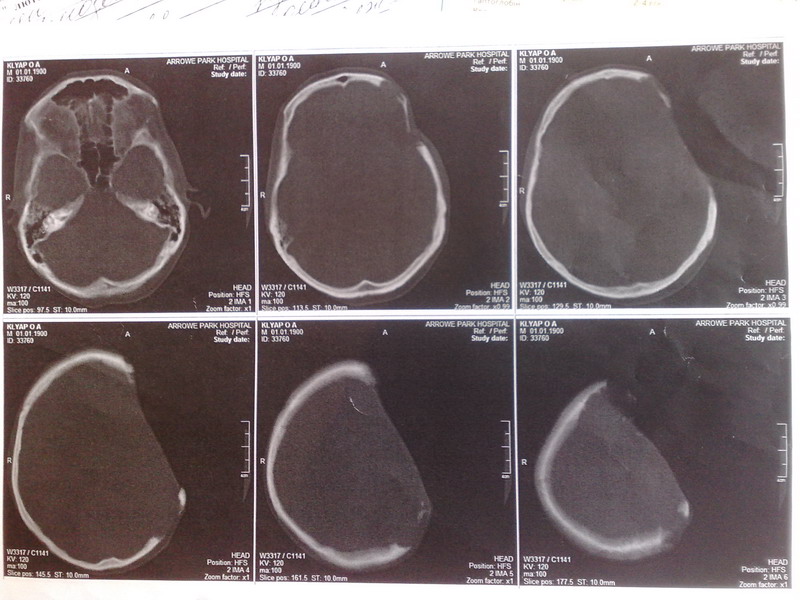

уже применить нельзя поскольку большой дефект кости. Ранее у больного была опухоль костей

черепа - солитарная плазмоцитома. Которая была удалена. Дефект был замещен протокриловым трансплантантом. Со временем произошло его отторжение.

За последний год дефект немного увеличился. Несколько дней назад было сделано КТ на котором

поражения головного мозга не обнаружено. Додаю результаты КТ.